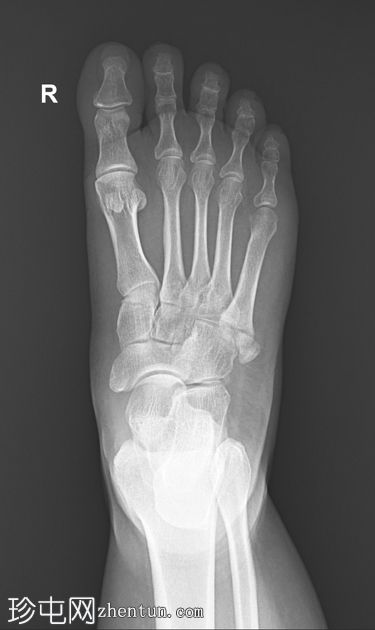

X线片

正位片

可见第五跖骨基底部粗隆(茎突)骨折。骨折线位于关节外,未延伸至第四至第五跖骨间关节。移位轻微。未见其他急性骨折。偶见腓骨副骨。